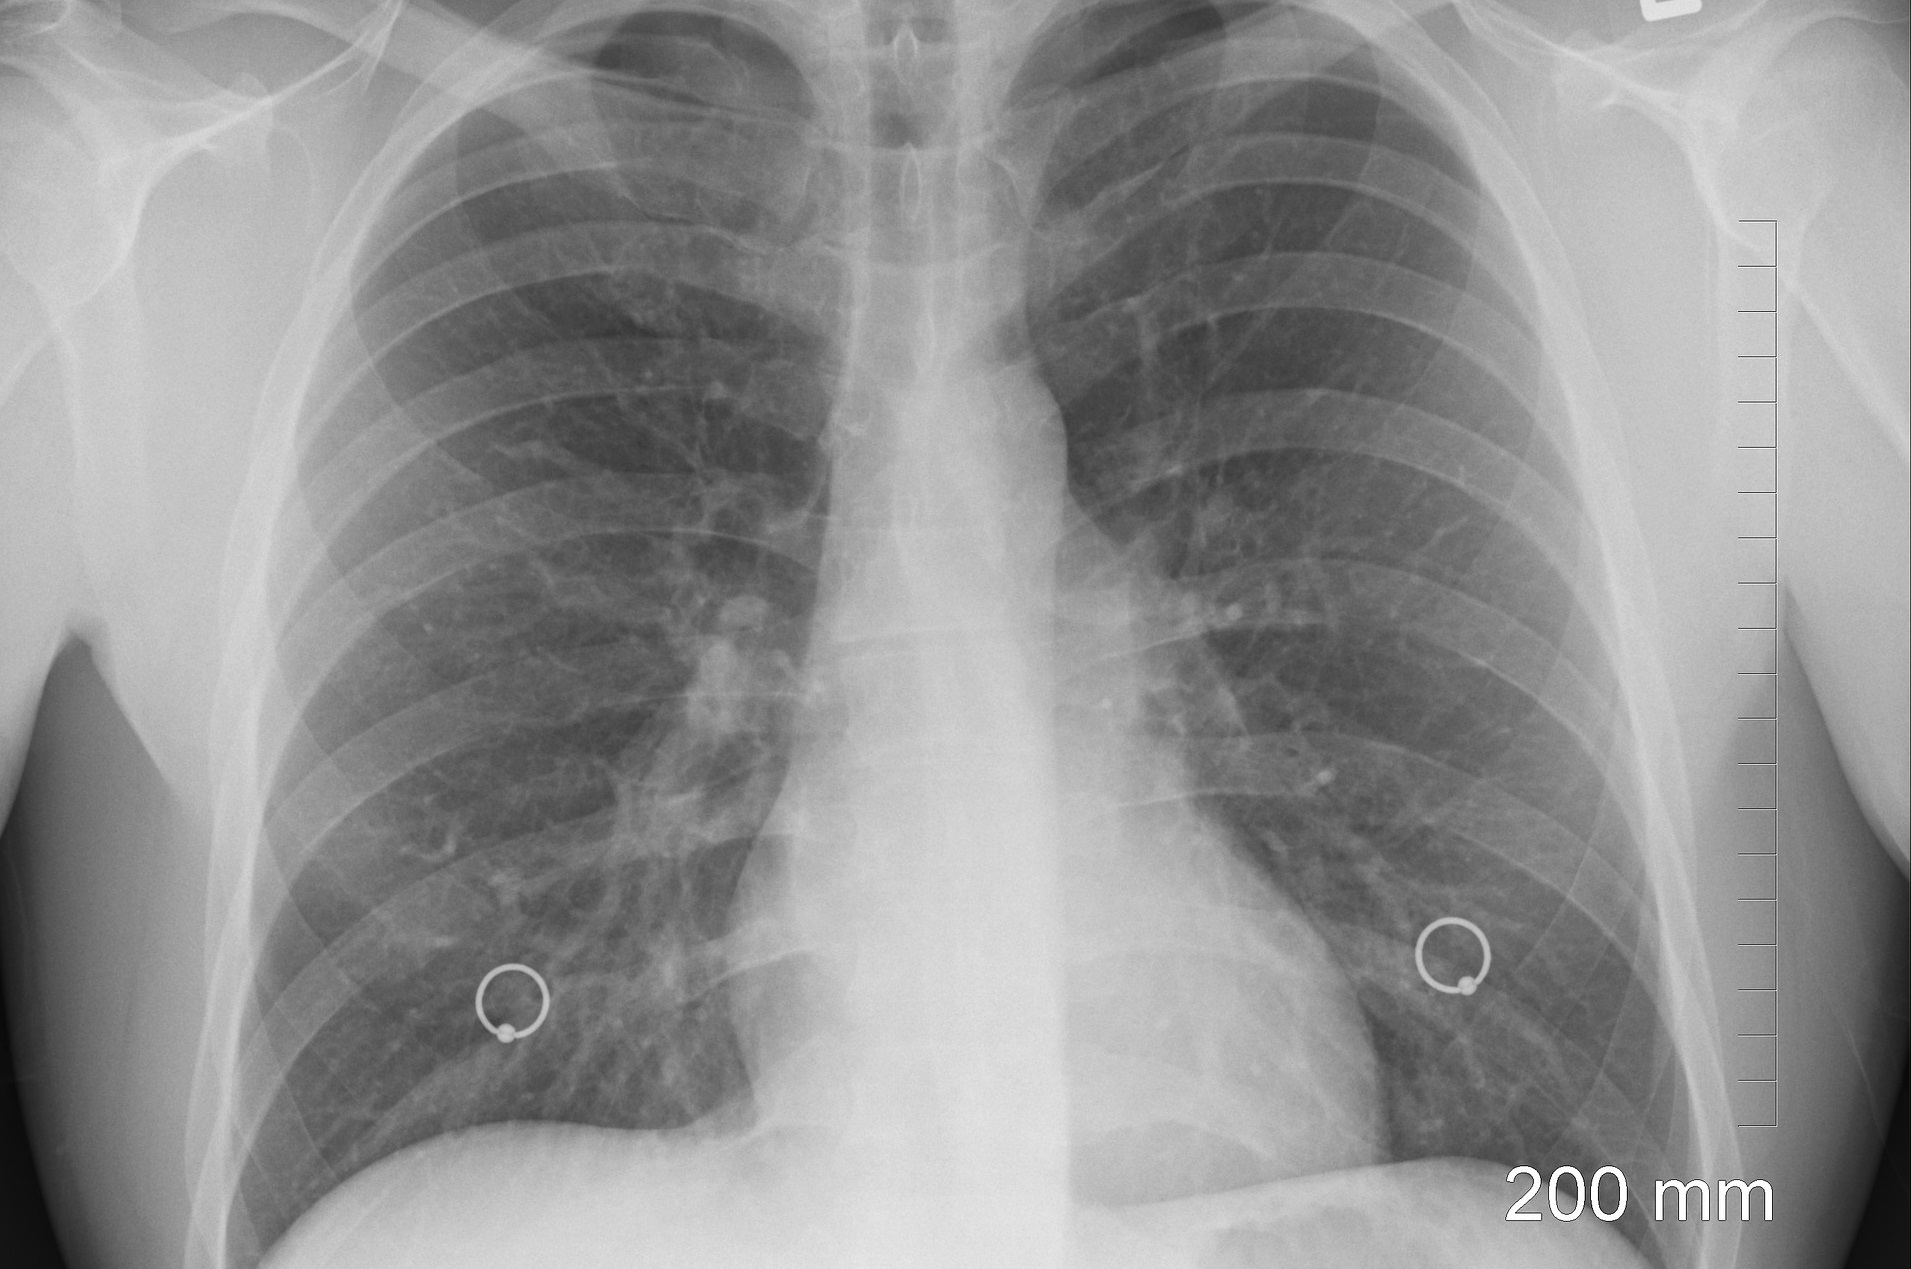

Sclerodermia, cunoscută şi sub denumirea de scleroză sistemică, aparţine unei familii de boli care afectează ţesuturile conjunctive din corp. Fibroza pulmonară poate fi secundară unei game largi de afecțiuni sau poate fi idiopatică, fără nici o cauză de bază cunoscută.

Ţesutul afectat şi cicatrizat devine rigid şi, prin urmare, plămânii nu mai funcţionează corect. Diagnosticul și gestionarea fibrozei pulmonare idiopatice suspectate ; Datorita unor mecanisme necunoscute, se produce o modificare lenta a structurii peretilor alveolelor pulmonare, care se ingroasa si devin rigizi.

Sclerodermia, cunoscută şi sub denumirea de scleroză sistemică, aparţine unei familii de boli care afectează ţesuturile conjunctive din corp. Datorita unor mecanisme necunoscute, se produce o modificare lenta a structurii peretilor alveolelor pulmonare, care se ingroasa si devin rigizi. Fibroze pulmonare produse de defecte alveolare difuze;

Fibroza pulmonara este caracterizata de cicatrizarea tesuturilor pulmonare si mai este cunoscuta sub denumirea de boala pulmonara interstitiala. Fibroza pulmonară este o boală respiratorie caracterizată prin întărirea și cicatrizarea țesutului pulmonar care înconjoară și interpune între alveole. Fibroza este consecinta inflamatiei.elementul central in aceasta teorie este macrofagul, care determina apel pentru neutrofile si eozinofile, dar si stimularea fibrogenezei.

Este o afecțiune cronică, cu evoluție progresivă, și în final letală, din pricina faptului că opțiunile de tratament sunt limitate. De asemenea fibroza pulmonara poate fi asociata cu infectii respiratorii (ca pneumonia ori tuberculoza). Consecinta este scaderea elasticitatii plamanului, lucru care incomodeaza respiratia.